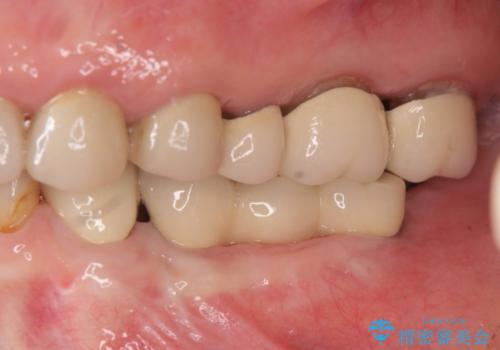

- 91万円(ストローマンインプラント×2・骨造成・チタンカスタムアバットメント×2・フルジルコニアクラウン×3)費用は治療当時の料金となります

インプラントを埋入することで入れ歯のように取り外しをする必要がなくしっかりと噛めるような状態になり、大変治療結果に満足していただくことができました。